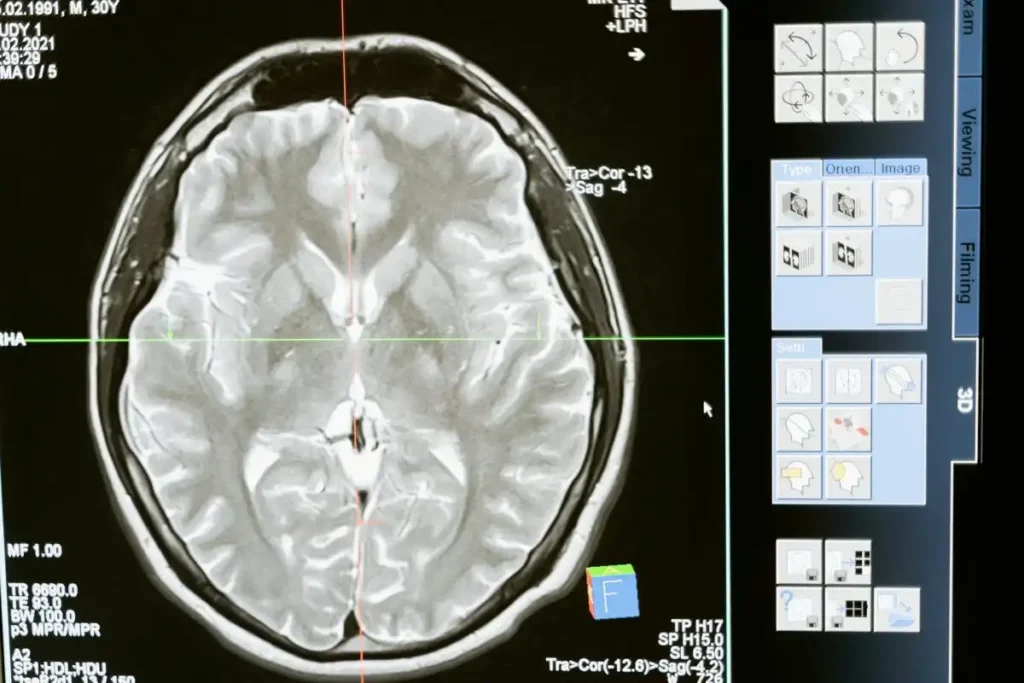

La epilepsia puede ser causada por diversas razones, y se estima que aproximadamente el 30% de los casos se deben a anomalías estructurales en el cerebro. Sin embargo, estas anomalías a menudo son difíciles de detectar en las resonancias magnéticas (IRM), especialmente las lesiones más pequeñas que pueden estar ocultas en pliegues cerebrales. Esto ha llevado a que muchos niños no sean considerados candidatos para cirugía, a pesar de que podrían beneficiarse enormemente de ella.

En el estudio, se incluyeron pacientes que sufrían de displasia cortical y epilepsia focal. Sorprendentemente, el 80% de estos niños había pasado previamente por una IRM cuyos resultados fueron considerados normales. Sin embargo, cuando los investigadores utilizaron la herramienta de IA para analizar tanto las IRM como otro tipo de exploración médica conocida como PET scan, la tasa de éxito en la detección de lesiones fue del 94% en un grupo de prueba y del 91% en otro. Estos resultados son impresionantes y sugieren que la IA puede ser una herramienta valiosa en el diagnóstico de la epilepsia.